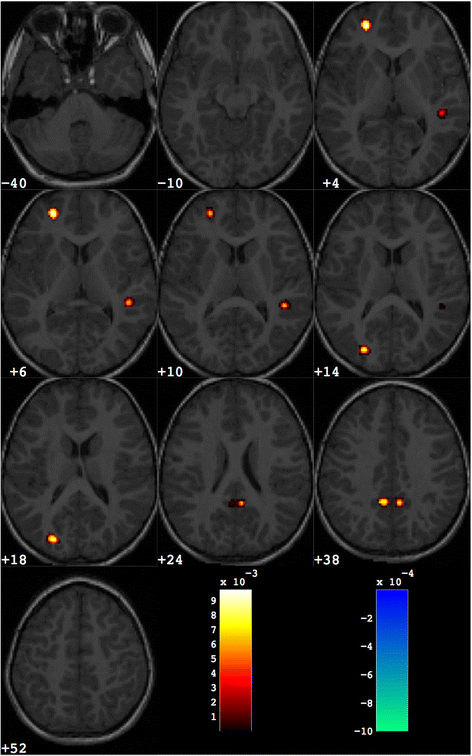

The discrimination maps obtained with the SVM-RFE procedure stopped at 1000 retained voxels are as many as the number of pairs contained in each dataset, as they are generated in LPC-CV (i.e. 38 maps for male and female datasets, 76 maps for the entire dataset). The sets of significant 1000 voxels in each map are in principle non consistent across all maps. However, as we observed, a strong similarity among all 1000-voxel discrimination maps, we adopted the restrictive criterion of considering only those regions with a non-null overlap across all maps. We reported in Additional file 2 an example of discrimination maps obtained at different values of n j obtained during the SVM-RFE procedure. The 1000-voxel discrimination map obtained with the above-described operations for the entire dataset of male and female subjects is reported in Fig. 2. Since it is possible to distinguish between the brain regions where GM is greater or lower in patients with respect to the control group when wi is positive or negative, in Fig. 2 these regions are separated using different colour scales (red and blue, respectively). In Table 3, the Talairach coordinates and the wi value of the centroid of these relevant regions are reported in addition to the anatomic labels assigned.

Fig. 2

Discrimination map obtained for the entire group of male and female subjects. About 1000 voxels are retained out of the total amount of grey matter voxels (more than 500,000). The map is overlaid to a representative structural MR image. The regions in red scale represent the brain areas where grey matter is greater in group with ASD with respect to controls; the regions in blue scale are referred to the opposite contrast

The discrimination map obtained for the male group of subjects is reported in Fig. 3. The relevant brain areas are listed in this case in Table 4. For the female group of subjects the discrimination maps and the list of relevant brain areas are reported in Fig. 4 and Table 5, respectively.